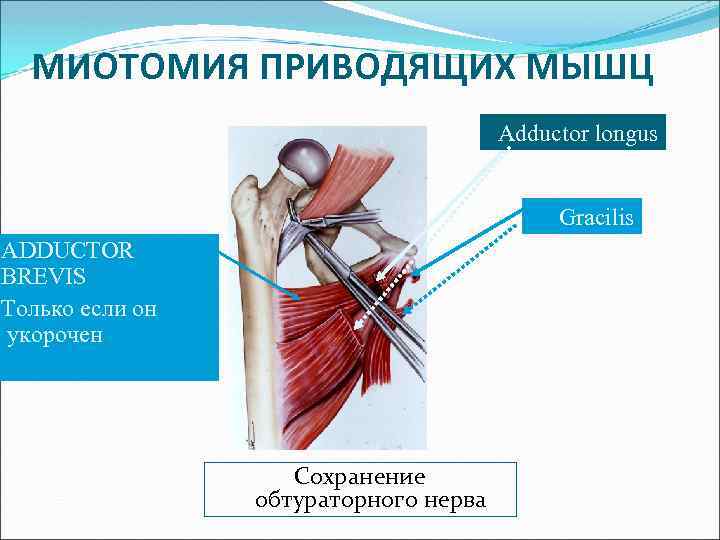

МИОТОМИЯ ПРИВОДЯЩИХ МЫШЦ -техника- GRACILIS ИСПОЛЬЗУЙ «ГОРЯЧИЙ НОЖ» ДЛЯ ПЕРЕСЕЧЕНИЯ МЫШЦ

МИОТОМИЯ ПРИВОДЯЩИХ МЫШЦ Adductor longus Gracilis ADDUCTOR BREVIS Только если он укорочен Сохранение обтураторного нерва